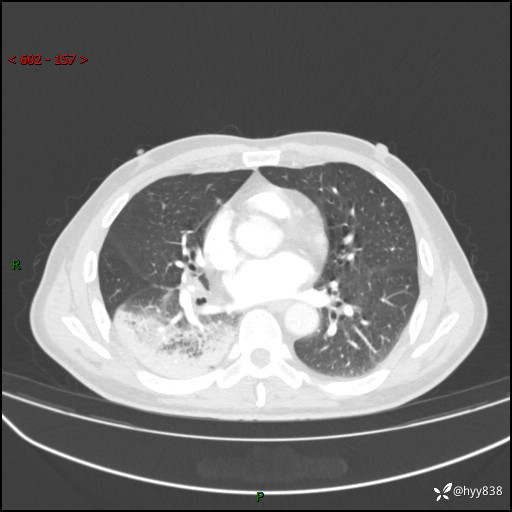

63岁/男,发热5余天。精彩好病例,“大叶性肺炎”,等你来诊---结果公布~

【患者信息】:63岁/男

【主诉】:发热5余天

【现病史及既往史】:患者5余天无明显诱因出现畏寒寒战发热,最高体温39.5℃,发热无明显昼夜规律,伴全身乏力、头晕,无头痛、无咳嗽咳痰、无胸痛咯血、无气短、无腹痛腹泻、无尿频尿急尿痛等不适,于当地市第五人民医院就诊,予以抗感染等治疗(具体不详)后发热无明显好转,1天前查胸部CT提示右下肺感染,为求进一步诊治,门诊以“社区获得性肺炎”收治入院; 起病以来,患者精神、食欲一般,睡眠可,大小便正常,体力体重较前无明显变化。

【检查】:胸部CT增强